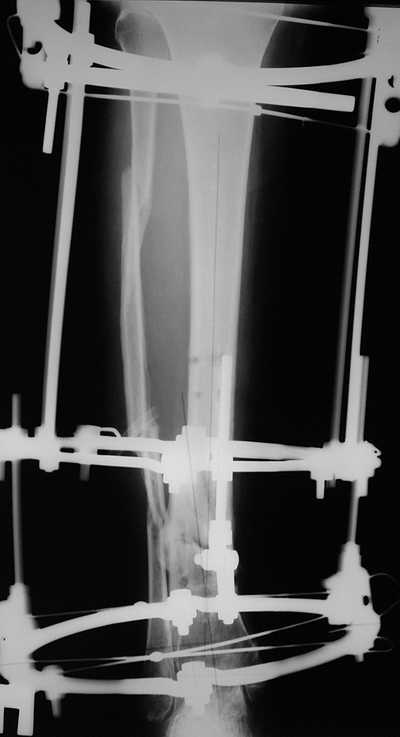

остеотомия м\б кости, аппарат Илизарова. По рентгенограммам в двух проекциях произведено планирование устранения смещений (рис 2 и 3), между вторым и третьим кольцом установлены 6 телескопических дистракторов Гесапода, данные введены в программу, и далее втечение 10 дней больная подкручивала телескопы согласно выданной компьютером инструкции. По завершению репозиции гексаподные телескопы обратно заменены на обычные штанги от аппарата Илизарова (рис 4 и 5). Еще через две недели забит гвоздь (рис 6, контроль

через 4 месяца).